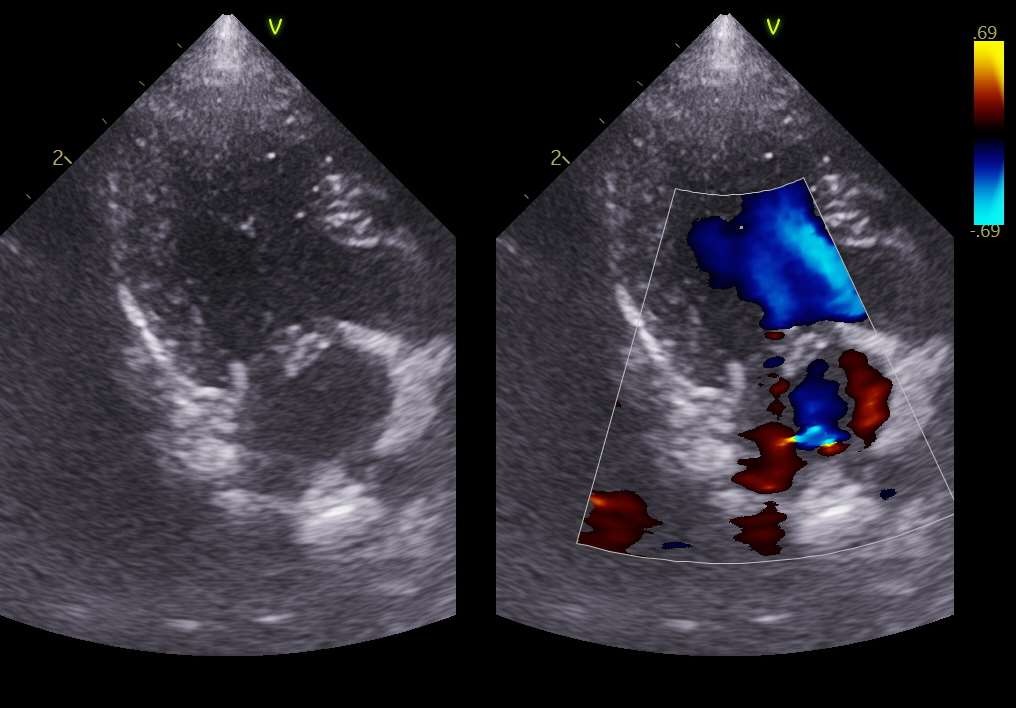

✔ 심장 검사

초기 단계의 심장 질환이 있었으나 적절한 모니터링 하에 마취 가능한 수준으로 판단되었습니다.

환자의 심장 검사 / 출처: 24시온숲동물의료센터